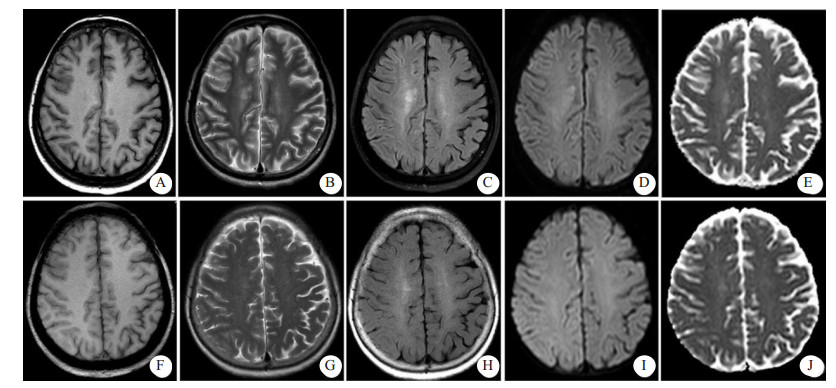

患者女性,71岁,2011年3月行食管癌切除术,6年来反复出现咯血症状,每次均在止血及抗感染治疗后好转。2018年1月20日患者再次出现咯血,入苏州大学附属第二医院介入科治疗。CT检查提示支气管扩张伴感染,遂于2018年1月25日在本院行支气管动脉栓塞术,分别对右支气管动脉远端、支气管动脉主干及左侧肋间动脉进行栓塞,术中使用的造影剂为碘海醇150 mL(浓度为30 g/100 mL)。术后仍出现反复痰中带血,因症状逐渐加重,患者于2018年8月13日再次来本院就诊。患者既往无高血压、糖尿病、心脏病等慢性病病史。入院后,给予患者头孢匹胺抗感染及止血、抑酸等对症支持治疗,咯血症状明显缓解。为进一步明确患者支气管动脉情况并予以处理,于8月17日穿刺右股动脉对患者施行支气管动脉造影+栓塞术,造影显示左侧两支支气管动脉与肋间动脉共干,左侧一支气管动脉血管明显增粗,紊乱,可见小片状可疑出血染色,遂对左侧两支与肋间动脉共干的支气管动脉分别予以栓塞,术中使用的造影剂为碘海醇100 mL(浓度为30 g/100 mL)。术中患者未有不适,术后患者安返病房。术后2 h, 患者无明显诱因下突然出现谵妄,查体:T 36.6℃,P 110次/min,BP 190/80 mmHg (1 mmHg=0.133 kPa),双侧瞳孔对光反射存在,左上肢肌力1级,右上肢肌力5级。急诊颅脑CT显示,右侧脑沟裂、纵裂池密度增高,局部脑实质肿胀、密度增高(图 1)。术后4 h颅脑MRI显示,右侧额叶部分皮质增厚,皮质T1WI信号稍减低,T2WI、T2WI-FLAIR、DWI信号增高,ADC信号稍高;右侧放射冠区见斑片状T1WI稍低信号,T2WI、T2WI-FLAIR、DWI高信号,ADC稍高信号影(图 2A~E);颅脑与颈部TOF-MRA显示各动脉未见明显扩张或狭窄征象。结合患者临床及影像学表现,在排除心脑血管病变后,经多学科会诊,考虑造影剂脑病。给予患者糖皮质激素抗炎、甘露醇降颅压、改善微循环及纠正电解质紊乱等对症处理,患者于术后第3天意识恢复,左侧肢体肌力明显好转。术后第6天,患者精神状态与左侧肢体肌力完全恢复,复查颅脑CT显示脑沟裂池内及局部脑实质高密度影消失,MRI各序列(图 2F~J)未见明显异常,予以出院,随访至今,患者未有不适。

| 患者介入栓塞术后2 h,示右脑沟裂、纵裂池密度增高(A),局部脑实质肿胀、密度增高(B) 图 1 患者颅脑CT检查结果 |